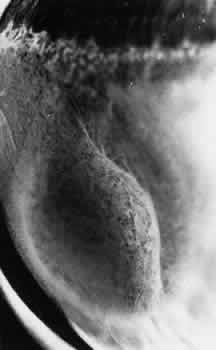

Fig. 12. Enclosed ora bay in a 35-year-old man. Anteriorly, two broad dentate processes converge and join to enclose a bay (island of pars plana). Posteriorly there is a focus of retinal thinning (peripheral retinal excavation; arrow). (× 12.)